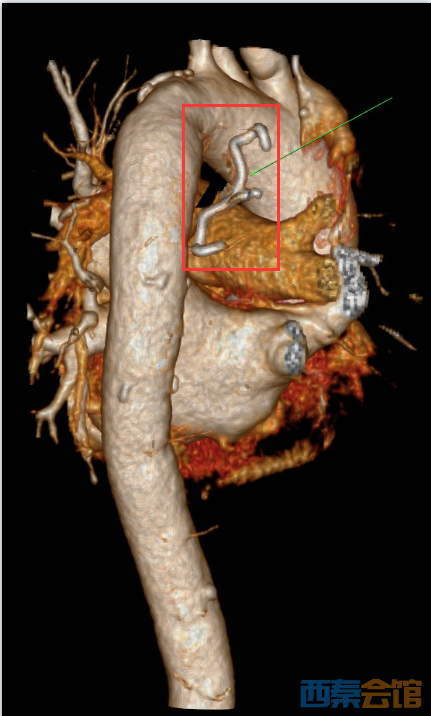

手术中,王茜结合CT判断出金属钩的大致形状,利用食管的走行,通过食管镜在狭小的空间内,慢慢调整金属钩的位置和角度……最终,金属钩被纵行还纳入食管,在有效的保护下,缓慢将它移出食管腔,最大程度地避免了二次损伤。当异物顺利取出的那一刻,王茜和手术室的所有人都如释重负。